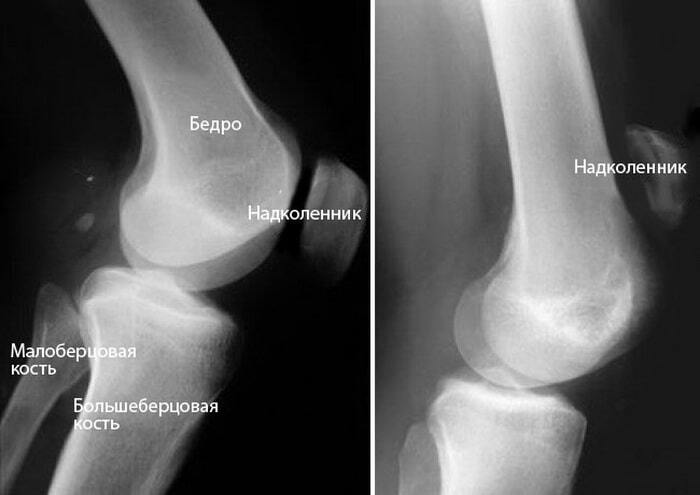

Писала пост месяц назад про болезнь Шлятера, как оказалось у меня скорее всего ее нет, мне не верно поставил диагноз  врач, который посмотрел и сказал просто ждать до 18 лет, тк у меня болезнь роста(сейчас 16, рост почти остановился).Сейчас пошла к другому и сделали МРТ, оказалось, что у меня хроническое воспаление, жутко смещён надколенник, под вопросом болезнь Кёнига и рассекающий остеохандрит, колени болят часто, так, что ходить почти не могу и хрустят сильно, болеть начали с 12 лет после травмы, а врачи ставили разные диагнозы при которых все должно было пройти за месяц или говорили, что я выдумываю, тогда тоже делали МРТ, были какие-то проблемы, но сейчас заключение МРТ стало больше в два раза(истощение хрящей, дегенеративное изменение связок). Хорошо диагностировали, почитала, что может быть некроз если не лечить эти болезни, начну лечение и оставлю в покое колени на месяц, надеюсь хоть в этот раз вылечусь или мне станет лучше.

2 фото то как выглядит мой надколенник, 1 то как должен выглядеть.